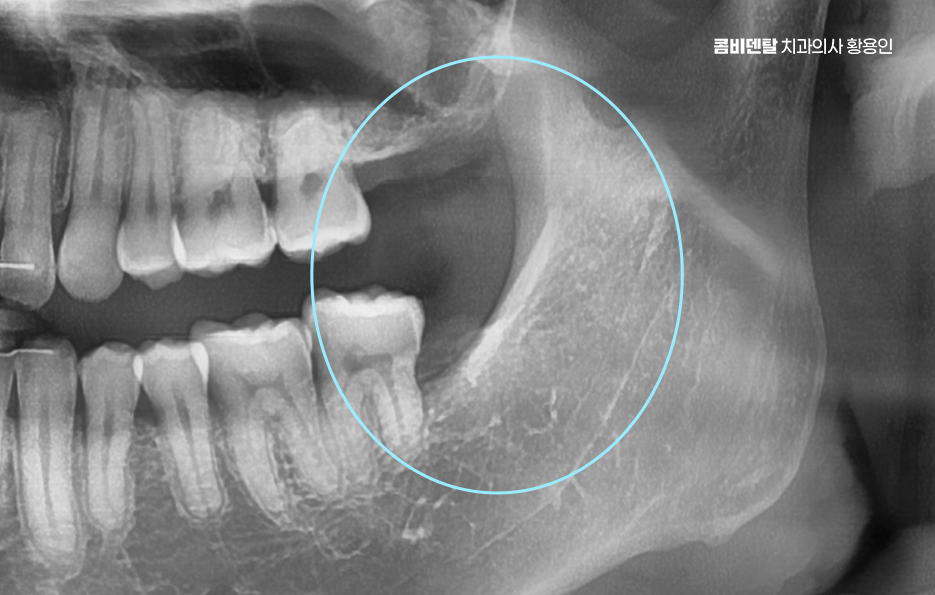

완전 매복사랑니는 보통 아래턱, 즉 하악의 뒤쪽에서 자주 발견되는데 위턱보다는 아래턱 뼈가 더 단단하고 구조적으로 복잡해서 발치 난이도가 더 높을 수 있으며 이 매복된 사랑니는 위치나 각도에 따라서도 발치의 난이도가 달라질 수 있었어요

여기에 더해서 신경과의 거리도 문제로 아래턱에는 하치조신경이라는 굵은 감각신경이 지나가는데 완전 매복사랑니의 뿌리가 이 신경과 가까이 위치해 있는 경우가 많아서 만약 발치 중 이 신경을 건드리거나 손상이 생기면, 입술이나 턱 끝 부위에 감각 이상이 생길 수 있어요.

완전매복사랑니 발치 그래서 무조건 바로 뽑는다고 되는 게 아니라, 사전에 정밀한 진단과 영상검사가 꼭 필요하며 일반적인 파노라마 사진 외에도 CT 촬영을 통해 신경과의 거리, 뿌리의 형태, 턱뼈의 두께 등을 정밀하게 확인해야 발치 계획을 안전하게 세울 수 있었어요.